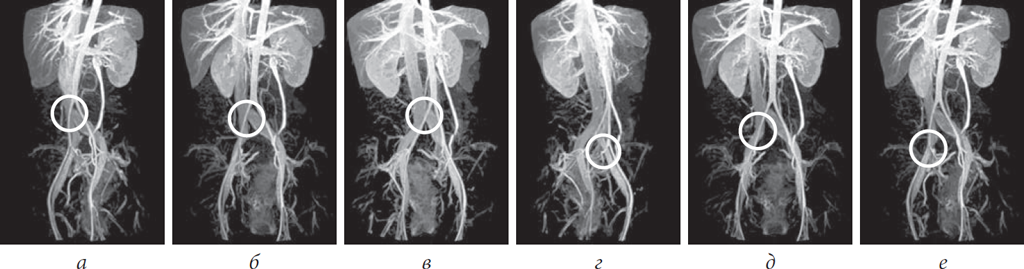

Проведенный нами анализ данных МРТ- и КТ-флебографий, а также рентгенконтрастных флебографий позволил предложить собственную классификацию артериовенозных конфликтов илеокавального сегмента:

- центральный проксимальный — высокая бифуркация аорты, при которой правая общая подвздошная артерия сдавливает нижний отдел нижней полой вены до ее деления на подвздошные вены (рис. 1, а);

- центральный дистальный — высокая бифуркация аорты, при которой правая общая подвздошная артерия сдавливает нижний отдел нижней полой вены в месте ее деления на подвздошные вены (рис. 1, б);

- левый проксимальный — правая общая подвздошная артерия сдавливает левую общую подвздошную вену (синдром Мея – Тюрнера) (рис. 1, в);

- левый дистальный — сдавление левой наружной и/или левой внутренней подвздошной артерией левой наружной подвздошной вены (рис. 1, г);

- правый проксимальный — сдавление правой общей подвздошной артерией правой общей подвздошной вены (рис. 1, д);

- правый дистальный — сдавление правой наружной и/или правой внутренней подвздошной артерией правой наружной подвздошной вены (рис. 1, е).

Рис. 1. Магнитно-резонансное исследование нижней полой вены и сосудов малого таза: а — центральный проксимальный артериовенозный конфликт илеокавального сегмента; б — центральный дистальный артериовенозный конфликт илеокавального сегмента; в — левый проксимальный артериовенозный конфликт илеокавального сегмента, или синдром Мея – Тюрнера; г — левый дистальный артериовенозный конфликт илеокавального сегмента; д — правый проксимальный артериовенозный конфликт илеокавального сегмента; е — правый дистальный артериовенозный конфликт илеокавального сегмента (моделирование)